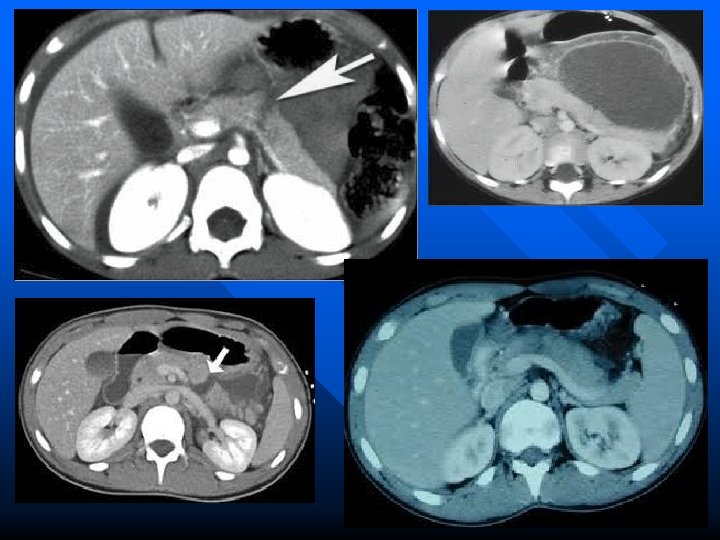

Radiographic Evaluation n Abdominal ultrasound – May be of limited value due to the presence of air and fluid within the bowel overlying the pancreas – May detect pancreatic edema n CT scan – Currently the most widely accepted and sensitive method used to confirm the diagnosis n MRI – Holds great promise – Results are equal to that of CT scan

Chronic Pancreatitis n Diagnosis – Is usually suspected on clinical findings – Routine laboratory tests are rarely helpful – Radiographic evaluation may reveal pancreatic calcifications on plain films – CT scan is useful in evaluating the size and texture of the pancreas – Endoscopic retrograde pancreatography – Pancreatic endocrine function

Periampullary Adenocarcinoma n n Difficult to differentiate from three other malignant periampullary neoplasms: ampullary carcinoma, duodenal carcinoma and carcinoma of the distal common bile duct Most common clinical features are jaundice, weight loss and abdominal pain Laboratory abnormalities include elevated serum bilirubin, alkaline phosphatase, CEA and CA 19 -9 Radiographic studies-upper barium series may be positive with large tumors, ultrasound may be of benefit and CT scan provides better accuracy of diagnosis

Adenocarcinoma of the Body and Tail of the Pancreas n n n Represents up to 30% of all cases of pancreatic carcinoma The tumors in this location usually grow quite large prior to becoming symptomatic These tumors do not cause early obstructive jaundice or GI obstructive symptoms Clinical presentation is usually weight loss and pain (90% of patients) Physical exam findings are often nonspecific CT scan is the best study for detection of primary and metastatic disease

Endocrine Tumors Rare with an incidence of five per one million n Endocrine tumors are named according to the major hormone produced by the tumor n Malignancy is determined by the presence of local invasion, spread to regional lymph nodes or hepatic/distant metastasis n Tumor localization is best identified using CT scan’s/MRI n

Diagnosis n n n No laboratory test is sufficiently accurate for the specific diagnosis of pancreatic injury Amylase is elevated in most patients with blunt trauma and only slightly elevated with penetrating injuries Peritoneal lavage is inaccurate because the pancreas is retroperitoneal Chest and abdominal films are often not helpful CT scan of the abdomen is gaining acceptance in evaluating pancreatic injury